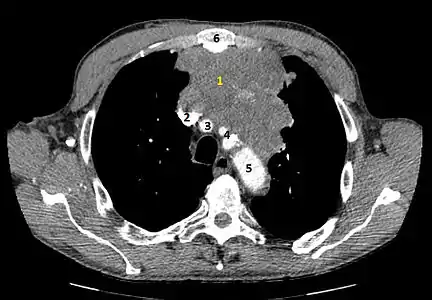

Présentation tomodensitométrique classique d'un thymome à un stade précoce (cercle rouge). À l'arrière, l'aorte, la veine cave supérieure et l'artère pulmonaire sont visibles en coupe. Scanner injecté, en fenêtre médiastinale, montrant un carcinome thymique envahissant les structures médiastinales :

Scanner injecté, en fenêtre médiastinale, montrant un carcinome thymique envahissant les structures médiastinales :

1 : tumeur hétérogène, aux contours irréguliers, présentant des plages hémorragiques ;

2 : veine cave supérieure ;

3 : tronc artériel brachiocéphalique ;

4 : artères sous-clavière gauche et carotide commune gauche ;

5 : crosse de l'aorte ;

6 : sternum. Scanner en fenêtre parenchymateuse, montrant un carcinome thymique envahissant les poumons (avec des lésions d'emphysème) au contact des deux poumons (1 : poumon droit ; 2 : poumon gauche) ;